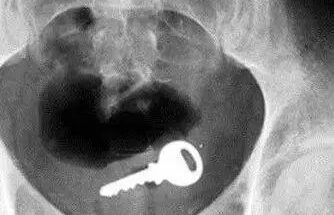

还有人开门,姿势太投入,一屁股坐进钥匙(我也不懂),现场目击者从嗑瓜子到集体失语……